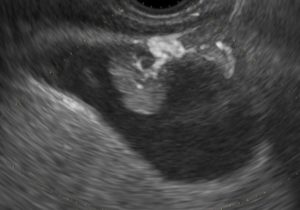

胆嚢癌?